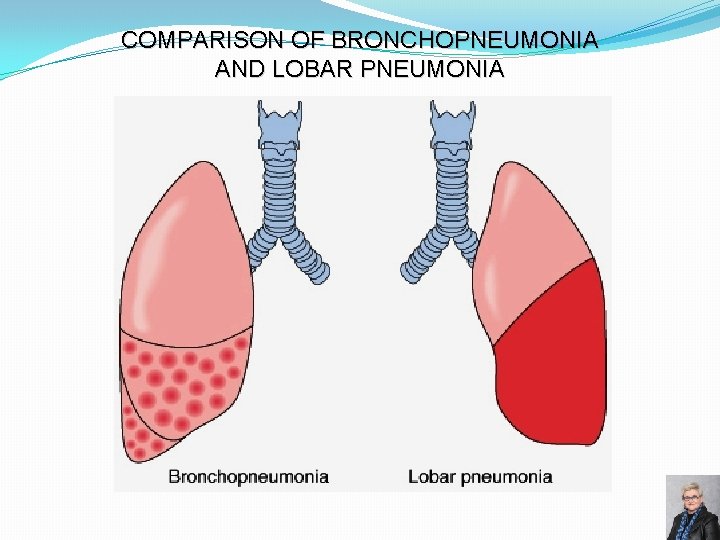

BRONCHOPNEUMONIA Gross morphology: � Scattered patchy consolidation centered around bronchioles – “lobular” pneumonia � Usually bilateral, multilobar and basilar Epidemiology: � Affects the young, old, and terminally ill Organisms: � Staphylococci, Streptococci, Haemophilus influenzae, � Pseudomonas aeruginosa and others Microscopic features: � Acute inflammation of bronchioles and the surrounding alveoli 67

COMPARISON OF BRONCHOPNEUMONIA AND LOBAR PNEUMONIA 74